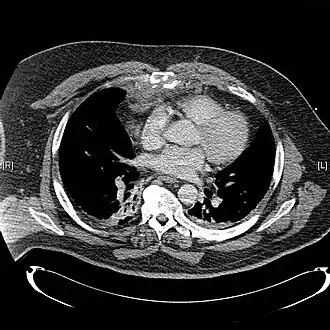

TDM d'une fracture comminutive du sternum avec un hématome rétrosternal[1]